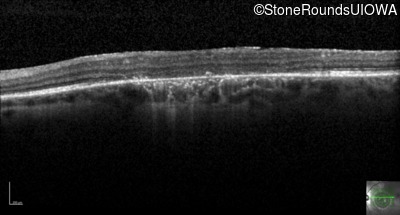

Optical Coherence Tomography - Right - 10/125 +1 sc

Exemplar / OCT Stack